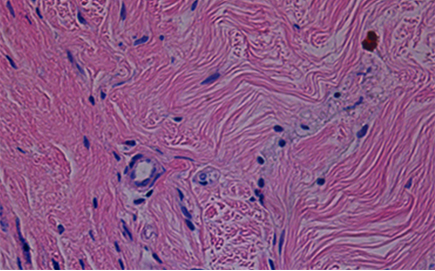

피부의 골격을 이루는 ECM(세포외기질)을 보존한 채 전달되어

처진 조직을 안정적으로 지지하고 피부 결, 탄력 등 동시 개선 효과 기대

쥬브아셀은 인체 유래 무세포 진피(haDM) 기반으로 피부 안정성을 높이고

콜라겐 · 엘라스틴이 풍부해 피부 본연의 밀도와 탄력을 회복시킵니다.